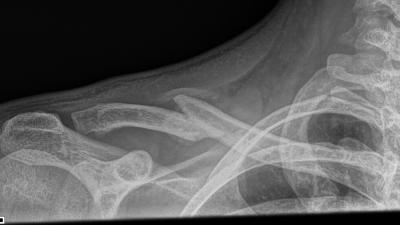

Een goed resultaat Sleutelbeen fractuur Lees meer

Sleutelbeen fractuur Sleutelbeen fractuur